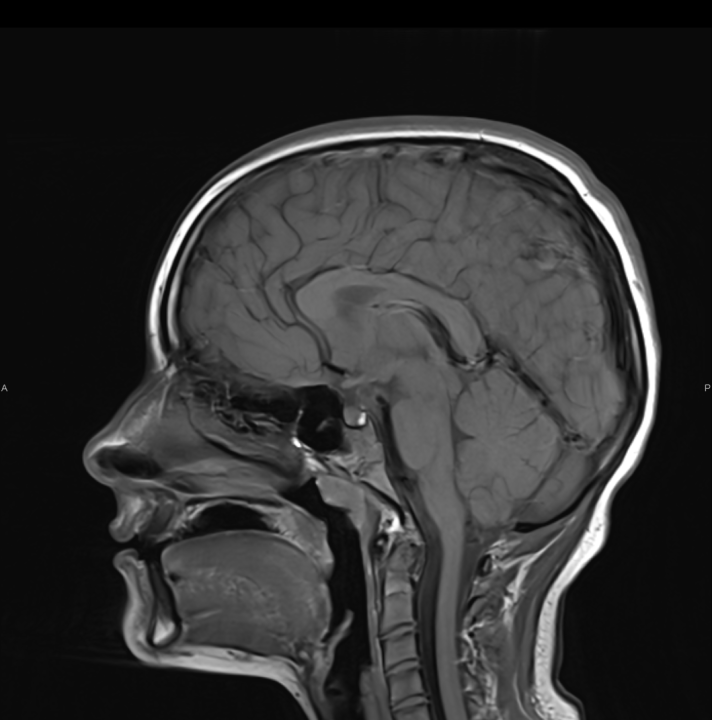

FOTO Naručite se na rendgen, ultrazvuk, CT ili MR u Poliklinici Affidea Vita!

FOTO Ako su vam potrebni specijalistički pregledi mamografija, RTG, UZV, CT i MR, koji se inače koriste za dijagnostiku velikog broja zdravstvenih problema, možete ih obaviti već danas ili sutra. Vodite računa o vašem zdravlju i zakažite pregled u Poliklinici Affidea Vita u Šibeniku na vrijeme!